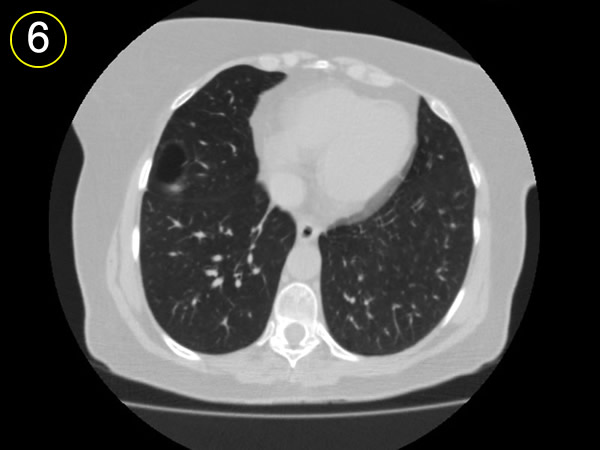

a-

segmento anterior del

lóbulo superior.

b-

lobulo medio

c-

segmento apical lobulo inferior

d-

bula subpleural